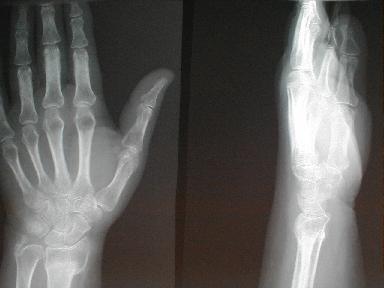

5月12日 受傷 96日目

日常動作には支障なく経過良好にて治癒とする